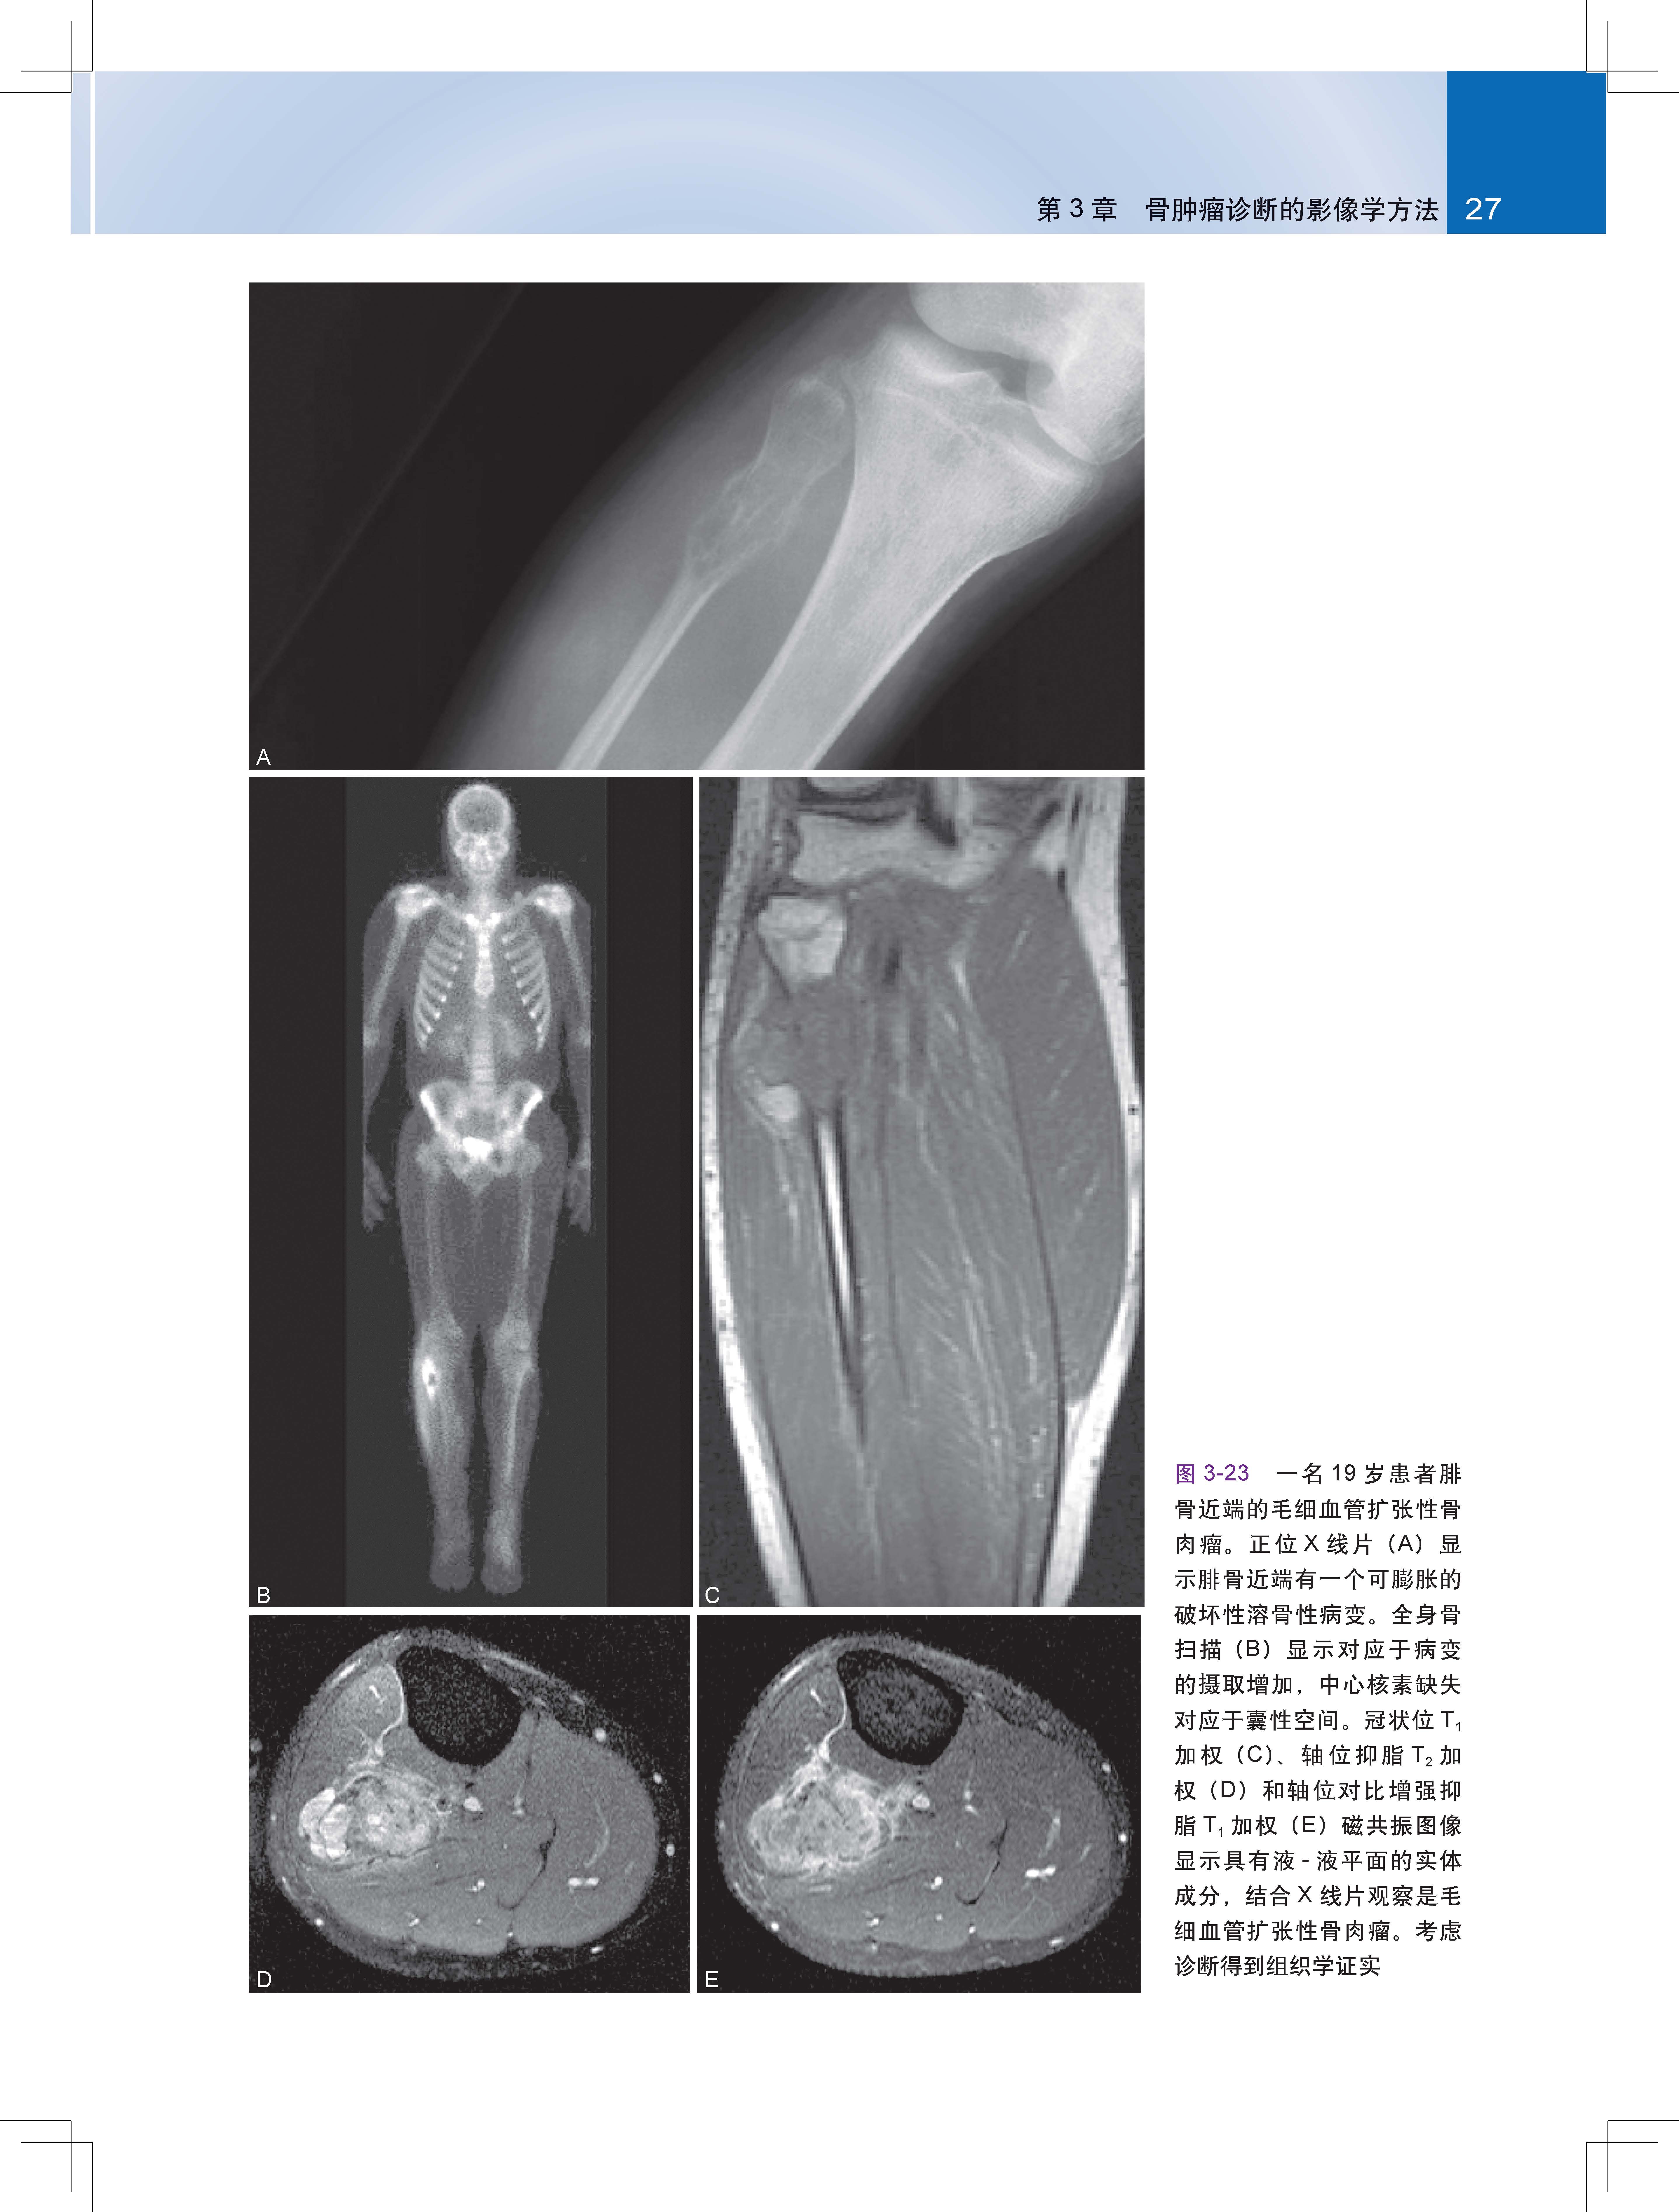

第3章 骨肿瘤诊断的影像学方法 10